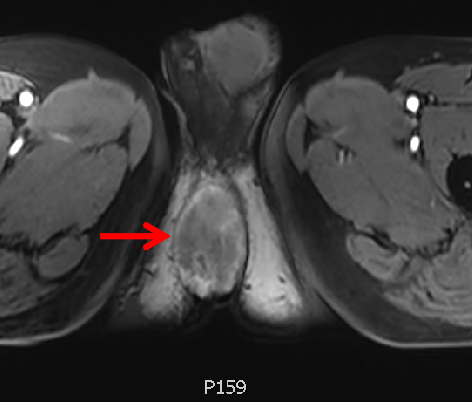

医学科影像

肛门右旁占位,考虑MT可能。